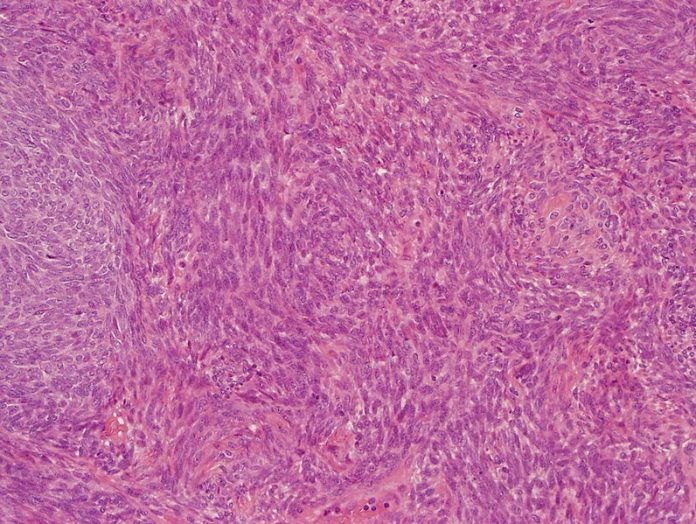

Il sarcoma sinoviale è una forma rara di cancro in cui le cellule maligne si sviluppano e formano un tumore nei tessuti molli. Può verificarsi in molte parti del corpo, sviluppandosi più comunemente nelle estremità. È un cancro potenzialmente pericoloso per la vita e ha un impatto devastante sugli individui. Ogni anno, il sarcoma sinoviale colpisce circa 1,000 persone negli Stati Uniti e si verifica più spesso nei maschi adulti sui 30 anni o più giovani.